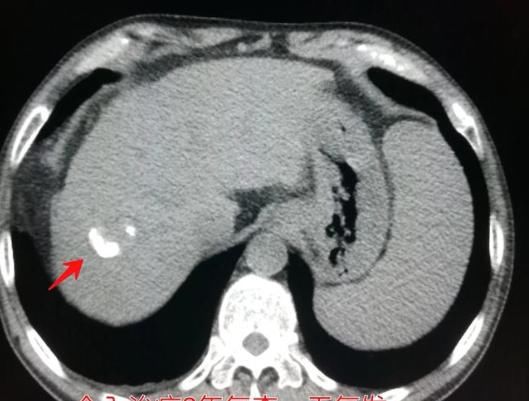

文章插图

这是一位肝硬化、脾大的病人,CT发现大量腹水和少量胸水,引起体重增加,但同时发现肝右叶肝癌。

他比较幸运,治疗效果很好!做了肝肿瘤动脉栓塞术和保肝、利尿治疗,两年多了没有复发: